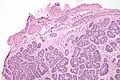

Micrograph of a Sertoli cell nodule. H&E stain.

A Sertoli cell nodule is a benign proliferation of Sertoli cells that arises in association with cryptorchidism (undescended testis).[1] They are not composed of a clonal cell population, i.e. neoplastic; thus, technically, they should not be called an adenoma.[2]

Sertoli cell nodules are unencapsulated nodules that consist of:[2][3][4]

- cells arranged in well-formed tubules (that vaguely resemble immature Sertoli cells), with

- bland hyperchromatic oval/round nuclei that are stratified, and

- may contain eosinophilic (hyaline) blob in lumen (centre).